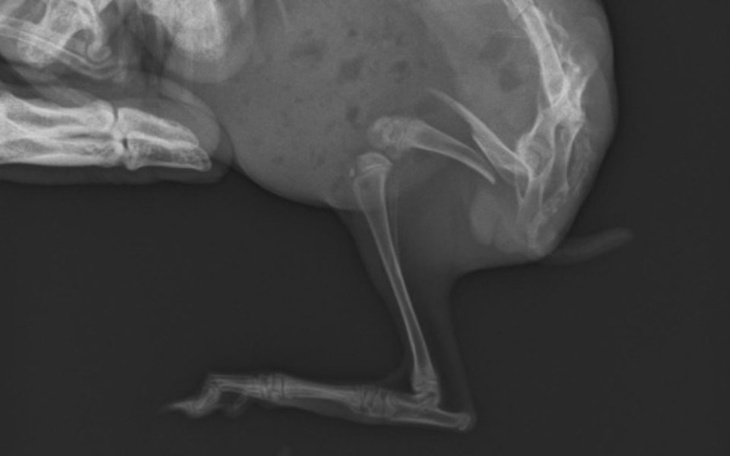

Mój krolik Leon złamal tylna łapkę. Ma dopiero miesiąc .jest bardzo żywym uszakiem .byłam u weteryniarza skierował go do ortopedy. Był i się załamalam jak usłyszałam jaka jest droga operacja.ale nie chce ze by się męczył 😢😢 jeśli możecie nam pomóc będziemy bardzo wdzięczni ☺